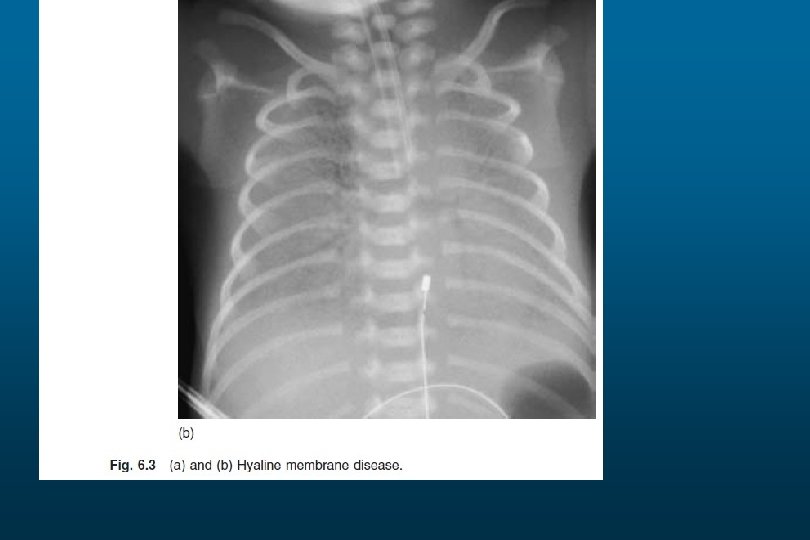

RDS